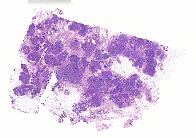

10518 |

右乳 |

女, 50岁, 因“发现双侧乳腺肿块1月”入院。患者1月前发现双侧乳腺蚕豆大... |

上海市同济医院 |

有诊断 |